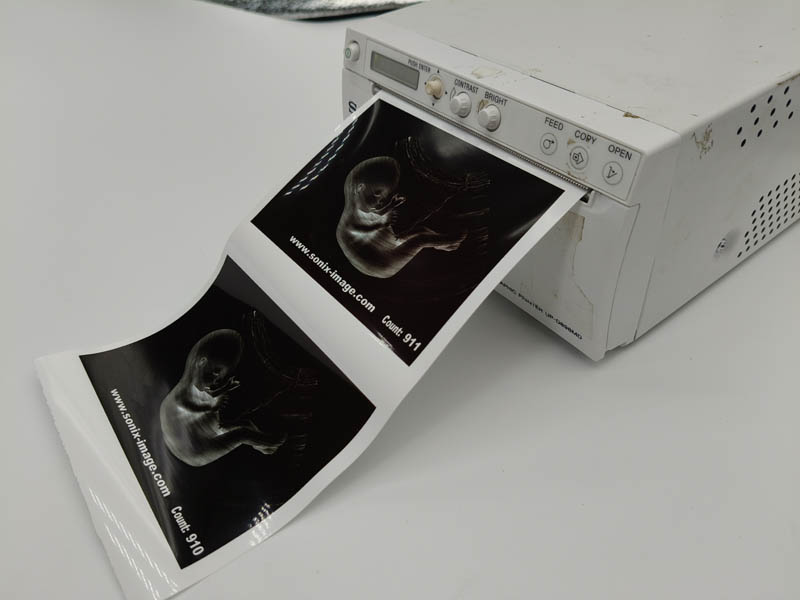

- Printing Effect for Our Type V video p